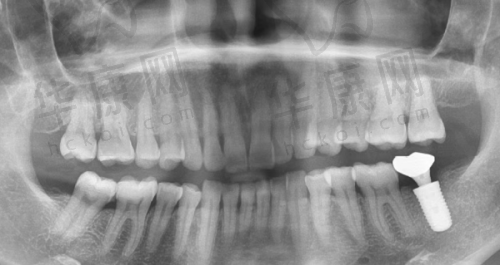

西藏拉萨雅博仕口腔医院杨彪仕诺康种植牙2998元起,这一优惠价格吸引了众多缺牙患者的关注。在口腔医疗领域,种植牙是一项重要的修复方式,而雅博仕口腔医院在这方面有着独特的优势。

在西藏拉萨雅博仕口腔医院,杨彪医生负责的仕诺康种植牙项目,单颗种植牙价格低至2998元起,这个价格包含了种植体、基台、牙冠以及手术费。相比市场上其他种植牙项目,这样的价格十分亲民。而且,医院的半口/全口种植套餐价格为3.2万元起,附加项目费用明细从600元起。此外,2025年该医院种植牙项目价格参考显示,单颗种植牙一般3000元起,具体取决于种植体选择、手术难度和患者口腔状况,韩国仕诺康种植牙2998元起/颗,韩国登腾种植牙3998元起/颗。

该医院的种植牙项目具有高原骨结合技术加持。患者选择仕诺康种植体 + 骨增量套餐,总费用比内地低40%。这一技术优势使得在高海拔地区的患者能够获得更好的种植成效,同时降低了治疗成本。在市场上,种植牙价格参差不齐,有的地方价格看似特别低,但技术和服务可能无法确保。而拉萨雅博仕的仕诺康种植牙2998元起,背后是可靠的技术、优质的种植体和贴心的服务。